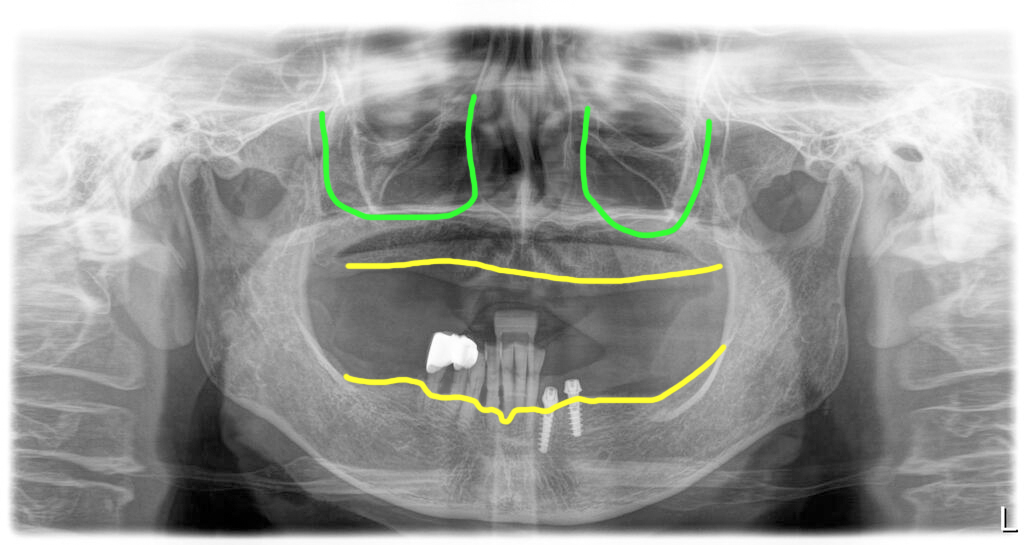

파노라마 엑스레이에서 보면 뼈가 충분해 보여서 쉽게 치료가 될 것으로 생각했지만 CT를 확인한 바 골의 폭경이 아주 좁아서 임플란트 식립에 어려움이 예상되었습니다.

파노라마 상으로 뼈가 좋아 보이지만

CT로 보면 골질이 안좋고 골폭이 좁아

그런데 CT상으로 관찰한 바로 뼈가 있기는 한데 굉장히 무른 상태이고, 폭이 매우 좁아져 있었습니다. 치아를 뽑고 틀니를 오래 사용하신 분들 중 이렇게 뼈가 많이 약해져 있는 경우가 많습니다.

골폭이 좁은 경우에는 뼈를 조심스럽게 쪼개어 임플란트를 고정시키게 됩니다. 그래서 보다 섬세한 수술 테크닉이 필요하게 됩니다.